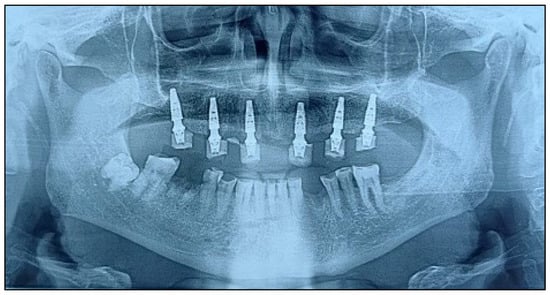

A CAD-CAM provisional prosthesis, designed from the digital wax-up, was prepared prior to surgery. Following implant placement, the provisional was secured using titanium cylinders and acrylic resin, adjusted intraorally to ensure passive fit and occlusal harmony. This prosthesis served as both a functional interim and a blueprint for the definitive restoration (Figure 10 and Figure 11).

Figure 10.

Postoperative orthopantomography with the implants in position and the provisional restoration in place.

Only two studies quantified positional deviations, recording mean coronal discrepancies of 0.95 mm and 0.87 mm, and angular errors of 2.8° and 2.67°, respectively—values well within the ≤1 mm/≤3° accuracy thresholds generally cited for full-arch guided surgery [,]. Across 351 implants, the global primary-stability targets clustered between 35 and 45 N cm, enabling immediate splinting in every case. The retrospective STAGE cohort experienced 10 early failures, yielding 96.5% survival at four surgical months [], while the remaining 67 implants placed in smaller series or single-case reports all survived, producing an overall cumulative survival of 97.1% at last follow-up [,,,,,,], as described in Table 2.

This protocol enabled immediate prosthetic loading using a preoperatively fabricated PMMA provisional restoration. The digital congruence between the surgical plan and prosthetic design minimized intraoperative adjustments and enabled accurate pick-up of temporary cylinders. This clinical outcome underscores the power of merging digital prosthodontics with stackable guided surgery to restore function, esthetics, and confidence in a single procedure. Therefore, the facially driven digital workflow combined with magnet-retained stackable guides offers a highly accurate, modular, and efficient method for full-arch rehabilitation. This case demonstrates how emerging technologies can reshape implantology by merging design, precision, and patient-centred care.

The coronal (≤1 mm) and angular (≈2.7–2.9°) deviations observed in the included stackable-guide studies are markedly lower than those reported for earlier tooth-supported stereolithographic templates, where Derksen et al. found mean entry and angular errors of 1.06 mm and 4.8°, respectively []. When the so-called “double-factor” workflow combined static guides with real-time navigation, Pomares-Puig et al. achieved 0.98 mm/3.7° accuracy but added hardware cost and setup time []. By contrast, Martins et al. used a fully digital, stackable All-on-4 protocol and reported no positional outliers or biological failures across 16 arches, indicating that rigid sequential templates alone can narrow the accuracy gap between static and dynamic systems without extra instrumentation [].